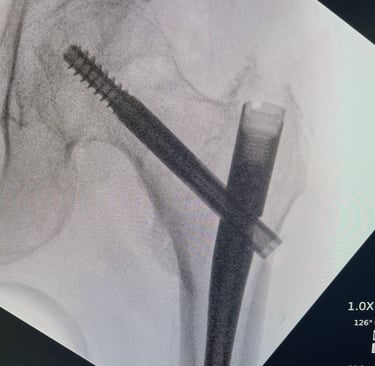

Mi occupo del trattamento traumatico sia in forma conservativa sia chirurgica. Tratto fratture, lussazioni, lesioni dei legamenti e dei tendini, con l’obiettivo di ripristinare la funzionalità articolare, ridurre il dolore e favorire un rapido ritorno alle attività quotidiane e sportive.